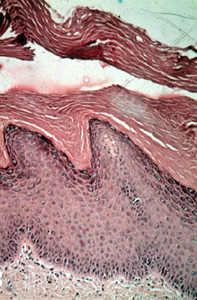

La diferencia entre la queratinización

y el epitelio no queratinizado se ilustra bien aquí. Los núcleos de

las células queratinizadas son más grandes y más prominentes; esto

proporciona la apariencia más oscura del tejido. Las células, sin

embargo, son bastante uniformes y no hay atipías. |